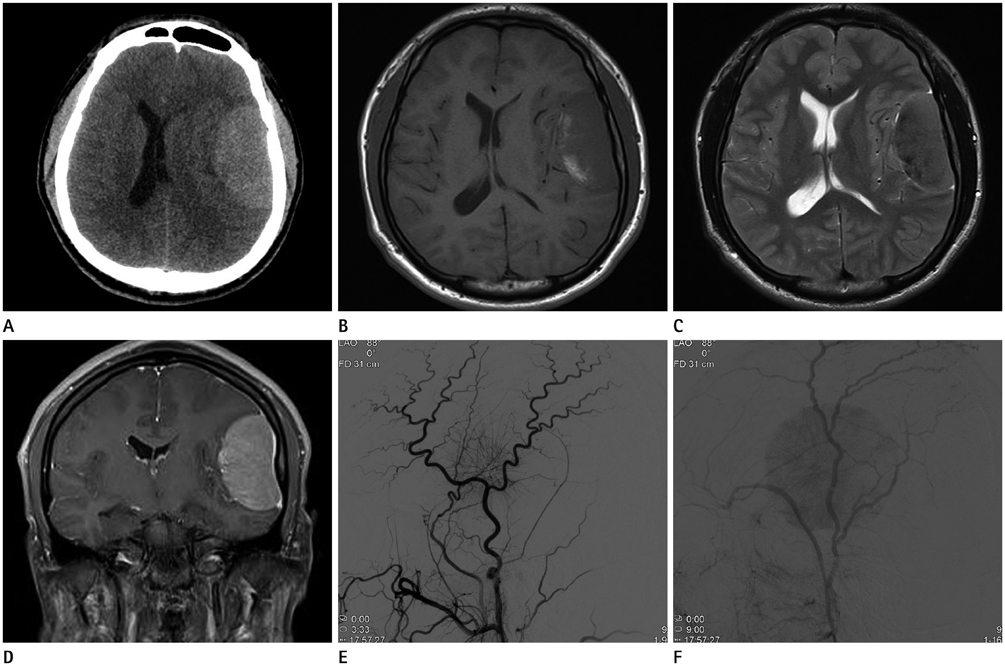

Dural Anaplastic Large Cell Lymphoma Mimicking Meningioma: A Case Report

- Anaplastic large cell lymphoma (ALCL) is a rare T cell lymphoma composed of CD30-positive lymphoid cells. Most ALCLs present as nodal disease, with skin, bone, soft tissue, lung, and liver as common extranodal sites. ALCL rarely occurs in the central nervous system and is even more infrequent in the dura of the brain. We report a case of dural-based ALCL secondary to systemic disease in a 17-year-old male that mimicked meningioma on magnetic resonance imaging and angiography.